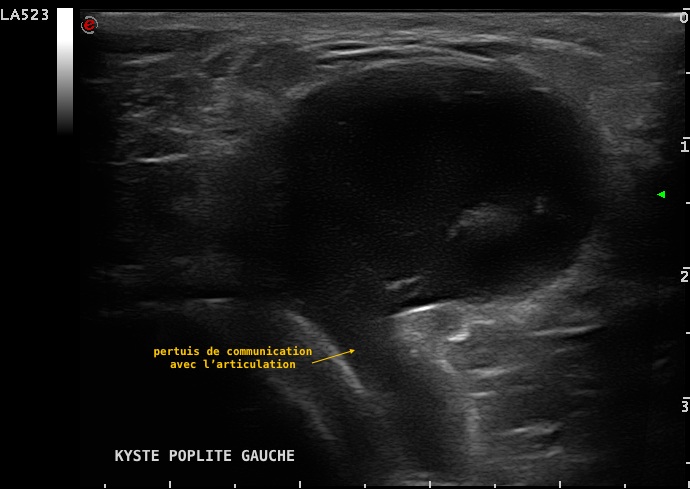

Volumineux kyste poplité symptomatique visualisé en échographie